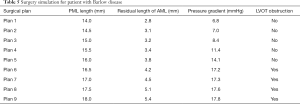

Of the 21 patients who were transferred to mitral replacement, there was one with Barlow disease (BD). The MV leaflets were redundant, with prolapse of P2 and P3. 3D-TEE showed billowing of both AML and PML, especially the P3 segment. Color Doppler showed severe MR originating from the PML. One challenge of repairing BD mitral valves is the development of postoperative SAM of the AML, which is often associated with a tall PML. As the height of the PML increases, the coaptation point gets closer to the base of the AML, and the length of the AML beyond the coaptation point (residual length) increases. Residual AML is free to move in response to the drag created by the jet flow, which can cause SAM and LVOT obstruction. We simulated the procedure with different PML lengths from 14.0 to 19.0 mm (with an 0.5 mm increase on each attempt). The residual length of the AML ranged from 2.8 to 5.4 mm (Table 5). The results show that SAM and LVOT obstruction occurred when the PML length reached 16.5 mm, with a residual length of the AML at 4.2 mm (Figure 8). The pressure gradient at the LVOT reached 17.2 mmHg after repair, but was only 6.8 mmHg before surgery.

Another patient, a 62-year-old woman, had a small left heart cavity, which is also a risk factor of postoperative LVOT obstruction. Echocardiography showed that the LV endsystolic dimension was 41 mm. Of note, the patient had suffered from hypertension for more than 10 years. The LA dimension was 36 mm (reference: 25–35 mm) and the ascending aorta dimension was 37 mm (reference: 23–32 mm). The interventricular septal (IVS) thickness was 14 mm (reference: 6–10 mm), which could increase the risk of LVOT obstruction after surgery. Firstly, we simulated MV repair in vitro without any intervention to the IVS. The results showed that pressure gradient at the LVOT reached 18.4 mmHg. We further attempted septal myectomy in the model (with 0.5 mm decrease of the IVS thickness on each attempt) and found an optimistic surgical outcome when the IVS thickness was less than 12.0 mm (Table 6, Figure 9). This suggested that conservative medical treatment (e.g., betablockers) or surgical intervention would be necessary to avoid adverse outcomes for this patient.

Complications following MV repair, such as LVOT obstruction, are another consideration for surgeons in their selection of procedure. Risk factors for LVOT obstruction include a tall PML (>1.5 cm), a ratio of AML to PML length >1.3, distance between the IVS and coaptation point (LVOT height) <2.5 cm, increased basal IVS thickness >1.5 cm, and small LV cavity (LV end-diastolic dimension <4.5 cm) (23,24). However, these standards are not absolute or applicable to every patient. In our study, we discussed 2 special cases of potential LVOT obstruction. One was a patient with BD, the other had a small heart cavity. LVOT obstruction occurred when the PML length was >16.5 mm in the BD patient, and when IVS thickness was >12.0 mm in the patient with a small heart cavity. This demonstrated the great potential and advantages of 3DP modeling and CFD in individualized diagnosis and treatment.